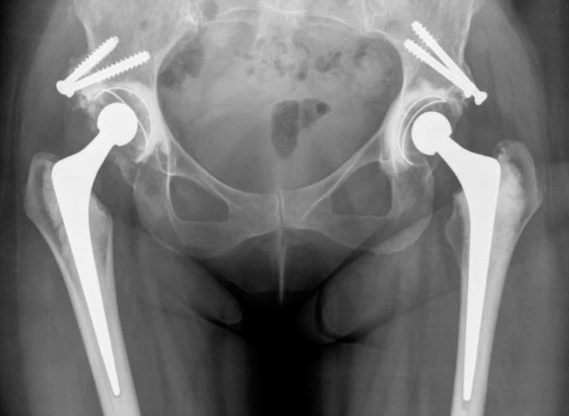

Complex hip replacement is a specialized surgical procedure designed for patients with hip joint issues that are more complicated than those typically addressed with primary hip replacement. These may include severe deformities, previous failed hip surgeries, hip fractures, or other complex conditions that require advanced techniques. Complex hip replacement surgery offers a solution to restore function, alleviate pain, and improve quality of life for patients who have more difficult or intricate cases.

Complex hip replacement involves replacing the damaged or diseased hip joint with an artificial prosthesis in cases where the hip joint has significant deformities, joint destruction, or complications from prior surgeries. The procedure is tailored to meet the unique needs of the patient, with an emphasis on addressing underlying conditions, repairing damaged tissues, and providing long-term stability.

3. Advanced Surgical Techniques: We utilize cutting-edge techniques and technologies to perform complex hip replacement surgery. This may include the use of custom implants, computer-assisted navigation, and minimally invasive techniques to reduce recovery times and improve outcomes.